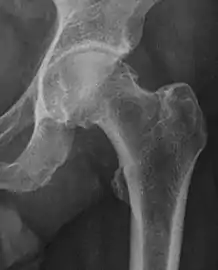

| Alpha angle | ![]() |

Degree of bulging of the femoral head-neck junction: In normal conditions there is a symmetric concave contour at the junction of the femoral head and neck. Loss of this concavity or bone bulging may lead to cam type impingement. The degree of this deformity can be measured by the alpha angle. Although it can be measured in the cross-lateral view, the 45° Dunn view is considered more sensitive and the frog leg view more specific in determining pathologic values. |

|